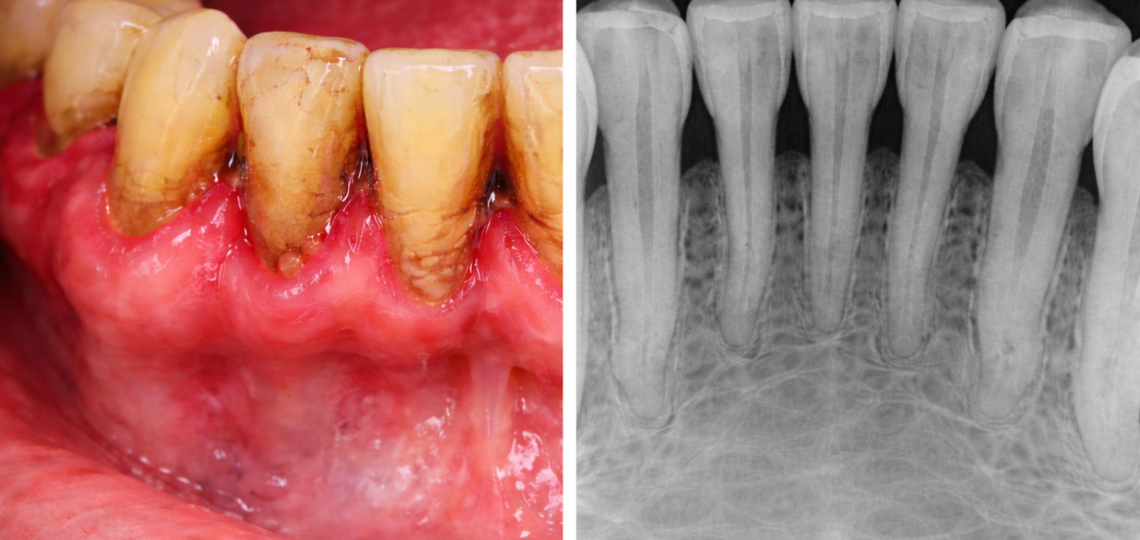

A doença periodontal é uma inflamação que afeta os tecidos de suporte dos dentes, ou seja, gengiva, ligamento periodontal e osso. Inicialmente, ela se manifesta como gengivite, que é uma inflamação superficial da gengiva. No entanto, quando não tratada, pode evoluir para periodontite, condição mais avançada que compromete o osso ao redor dos dentes.

Gengiva inchada ou avermelhada

A gengiva saudável apresenta coloração rosada e textura firme. Quando há inflamação, ela se torna edemaciada, sensível e mais escura.

Retração gengival

Com a progressão da periodontite, a gengiva pode retrair, expondo a raiz do dente e aumentando a sensibilidade.